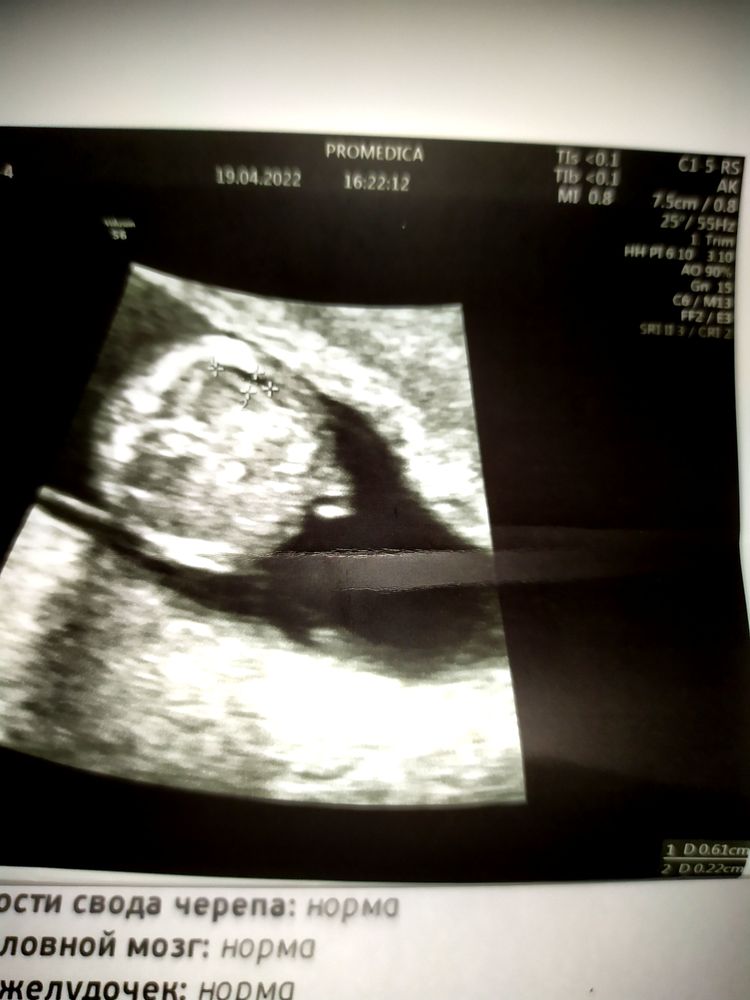

Gular Guliyeva, сегодня была в ПЦ, там генетик намерила, ктр 78 - 14 недель, твп 2.3, сказала гиперэхогенные почки, лоханки 1.3, легкие гиперэхогенные и жидкость в брюшной полости 3 мм.

Я в слезах побежала к др. врачу, тот тоже опытный, крутил, вертел... Написал твп - 2 мм, лёгких гиперэхогенных не нашёл, почки чуть эхогенные, лоханки не расширены, 1 мм, а вот жидкость... Сказал точно что-то есть, как узкая полосочка... Ну фото вы видите, я боюсь хромосомных аномалий, так как в интернете пишут именно это.